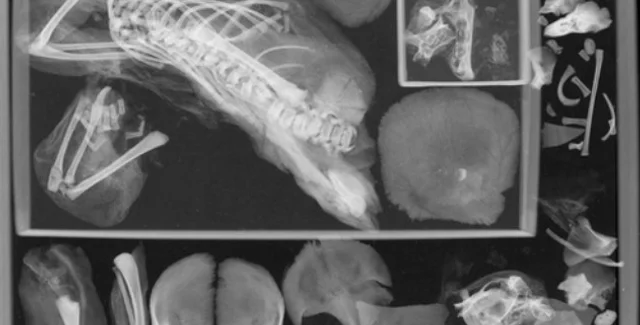

Останки другого плода було знайдено в грудній порожнині матері | Фото: International Journal of Osteoarchaeology

Останки другого плода було знайдено в грудній порожнині матері

Фото: International Journal of Osteoarchaeology

Результати томографії засвідчили, що в грудній порожнині підлітка містяться предмети, які не належали плоду, знайденому поруч з останками матері. Марголіс продовжила дослідження разом з антропологом Університету Джорджа Вашингтона Девідом Хантом: вони виявили, що в грудній порожнині муміфікованого тіла перебували рештки другого плода — схоже, ніхто не знав, що дівчина була вагітна двійнею.